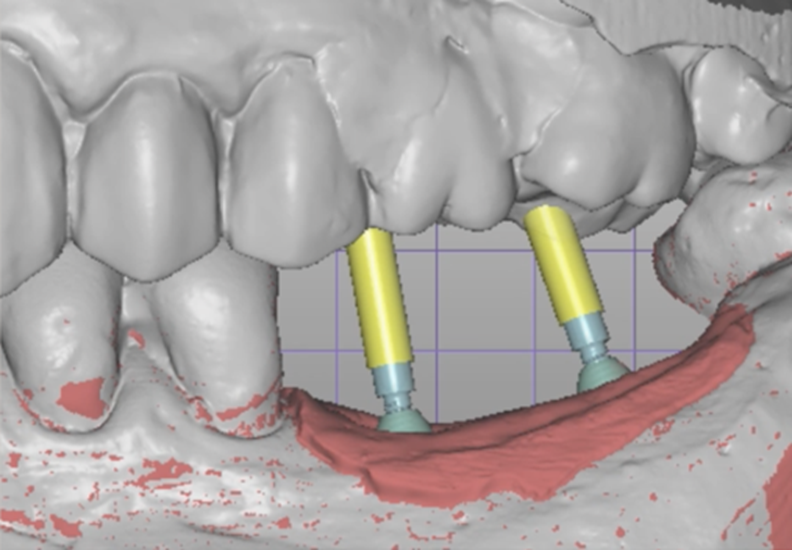

As duas formas em que o implantodontista e o protesista podem trabalhar sobre este componente estão inseridas na biblioteca do Exocad (principal software que é utilizado nos laboratórios). Se seguirmos no caminho de confeccionar a prótese múltipla diretamente sobre o componente, utilizaremos o transferente digital sobre a “cabeça” do Mini Cônico e na hora de enviar para o laboratório o arquivo STL do escaneamento, informaremos para o Cadista que realizamos a moldagem digital (CAI) do componente.

Se seguirmos o caminho de escaneamento do Transfer Digital Mini Cônico, poderemos definir no Exocad se faremos aplicando o Base T Mini Cônico na estrutura ou se faremos a peça em zircônia sem utilização do Base T Mini Cônico, conforme seleção da biblioteca Exocad.

Na etapa de escaneamento foi selecionado o transferente digital do Mini Cônico e optamos por trabalhar no fluxo e biblioteca do software Exocad (onde é realizado o design da prótese), o qual tem toda a linha de componentes da Implacil De Bortoli e de seus análogos digitais.

Neste caso, a prótese múltipla foi desenhada sobre o Mini Cônico e as duas coroas foram fresadas unidas. Após a maquiagem final da zircônia monolítica, as coroas foram parafusadas sobre o Mini Cônico com um torque de 10 Ncm.

Podemos acompanhar o passo a passo das etapas, desde a seleção da altura do transmucoso do Mini Cônico até a instalação das coroas unidas no fluxo totalmente digital sem a utilização de componentes metálicos.